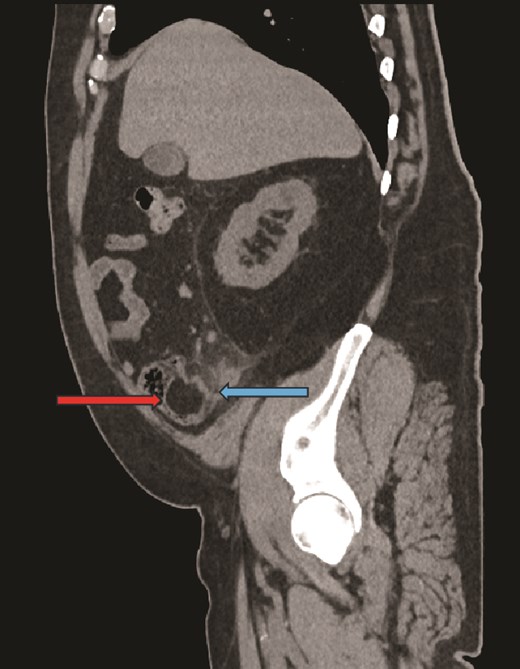

Sagittal CT image, showing caecal lipoma (right arrow) and appendicitis (left arrow).